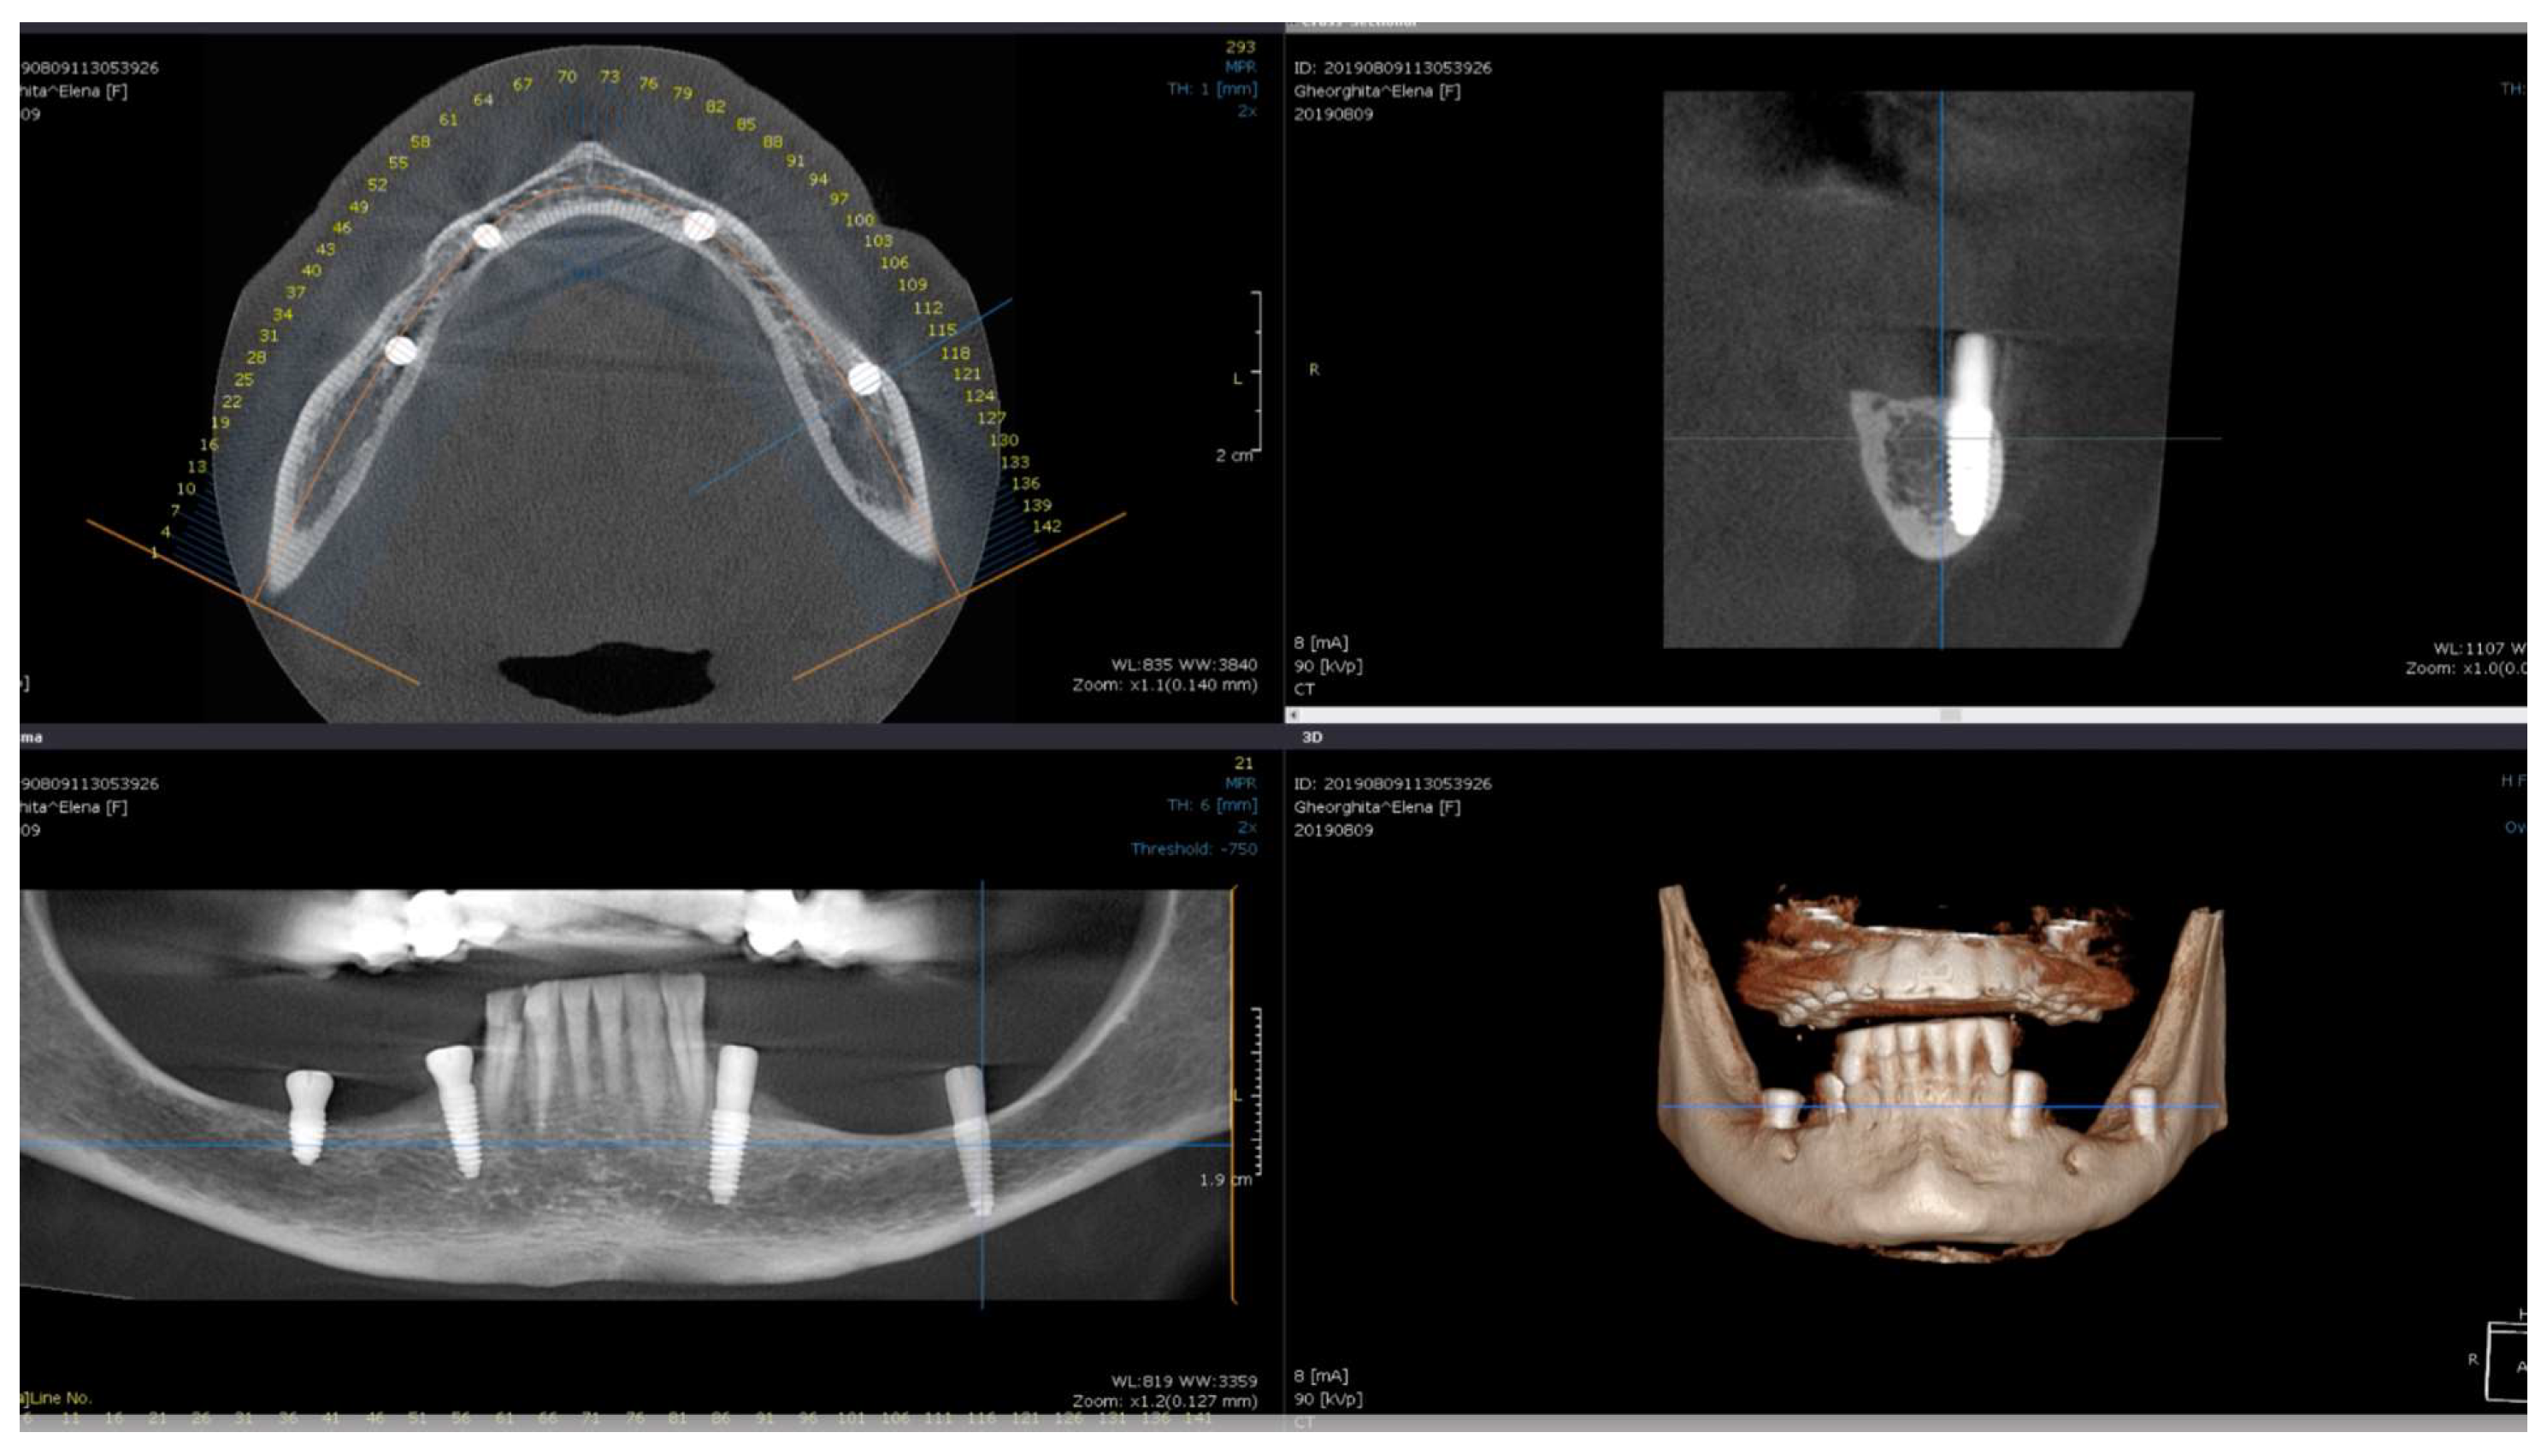

Direct visual access to the residual bone was obtained by elevating a full muco-periosteal flap. A lance drill was used to mark the implant site at approximately 2 mm towards the midcrest with respect to the buccal or lingual cortex. To avoid thermal osteonecrosis, copious cooling irrigation, new drills, and a maximum speed of 800 RPM were used for implant site preparation. After the osteotomy site was marked, a pilot 2 mm drill was selected to perform the preparation for the length of the selected implant. In-and-out manoeuvres were performed in order to facilitate cooling of the drills. If the implant is planned to be placed buccally, the drill must be oriented with the apex faced towards buccal wall, trying to keep the axis of the drill parallel to the buccal cortex. In most of the cases, if the pilot drill direction was properly assessed, minimal or even no bleeding will be observed and the patient will indicate no pain. If the osteotomy preparation was performed buccally, a bone dehiscence might be present. In this scenario, the following drills must be slightly pressed towards the inner wall (wall facing towards the middle of the alveolar crest) of the osteotomy site. This manoeuvre is performed by a digital propelling force on the head of the handpiece, according to the preparation protocol for D1 bone recommended by the implant company. If a 4.0 mm diameter tapered implant (AnyRidge, Megagen Implant Co., Daegu, Republic of Korea) is planned to be used, the following drills were selected for convenient site preparation: 2.7 mm, 3.3 mm, 3.8 mm for the whole length of the osteotomy and a 4.3 mm drill was used only for countersink. Implant insertion was done with the surgical motor (at 35 RPM). A similar drilling protocol is applied for 3.5 mm diameter implants (last drill 3.3 mm and 3.8 mm countersink) and a 4.3 mm drill for the whole length, for 4.5 mm diameter implants. Depending on the thickness of the surrounding soft tissues and the relation with the buccal mucosa, either a 7 mm long healing abutment (I-Gen Kit, Megagen, Daegu, Republic of Korea) or a customized healing abutment was connected to the implant, with digital clockwise rotations. Double layer suture (horizontal mattress and simple suture) was done with 5/0 resorbable suture (Vicryl, Ethicon, New Brunswick, NJ, USA). Patients were prescribed antibiotics (Augmentin®—amoxicillin plus clavulanic acid 1 g/every 12 h) and one tablet of anti-inflammatory drug (Ibuprofen 600 mg at every 8 h) for the following 5 days. Patients were instructed to avoid brushing the neighbouring teeth in the treated area and chlorhexidine solution (0.12%) was prescribed for daily usage (twice a day for 1 min). Sutures were removed after 14 days [16]. All patients were recalled for clinical checkup 1 day, 1 week, 2 weeks, and 2, 6, 12, 24, and 36 months after surgery. All complications, both during the surgery and postoperative, were reviewed. A postoperative CBCT was done to assess implant positioning. Buccally tilted and lingually tilted implant positioning are presented in Figure 1 and Figure 2, respectively.

Figure 1.

Postoperative CBCT of patient no. 6: (Upper left)—axial view of the mandible; (upper right)—sagittal left view of the buccally tilted implant (37); (lower left)—coronal view of the mandible; (lower right)—3D view of the mandible.